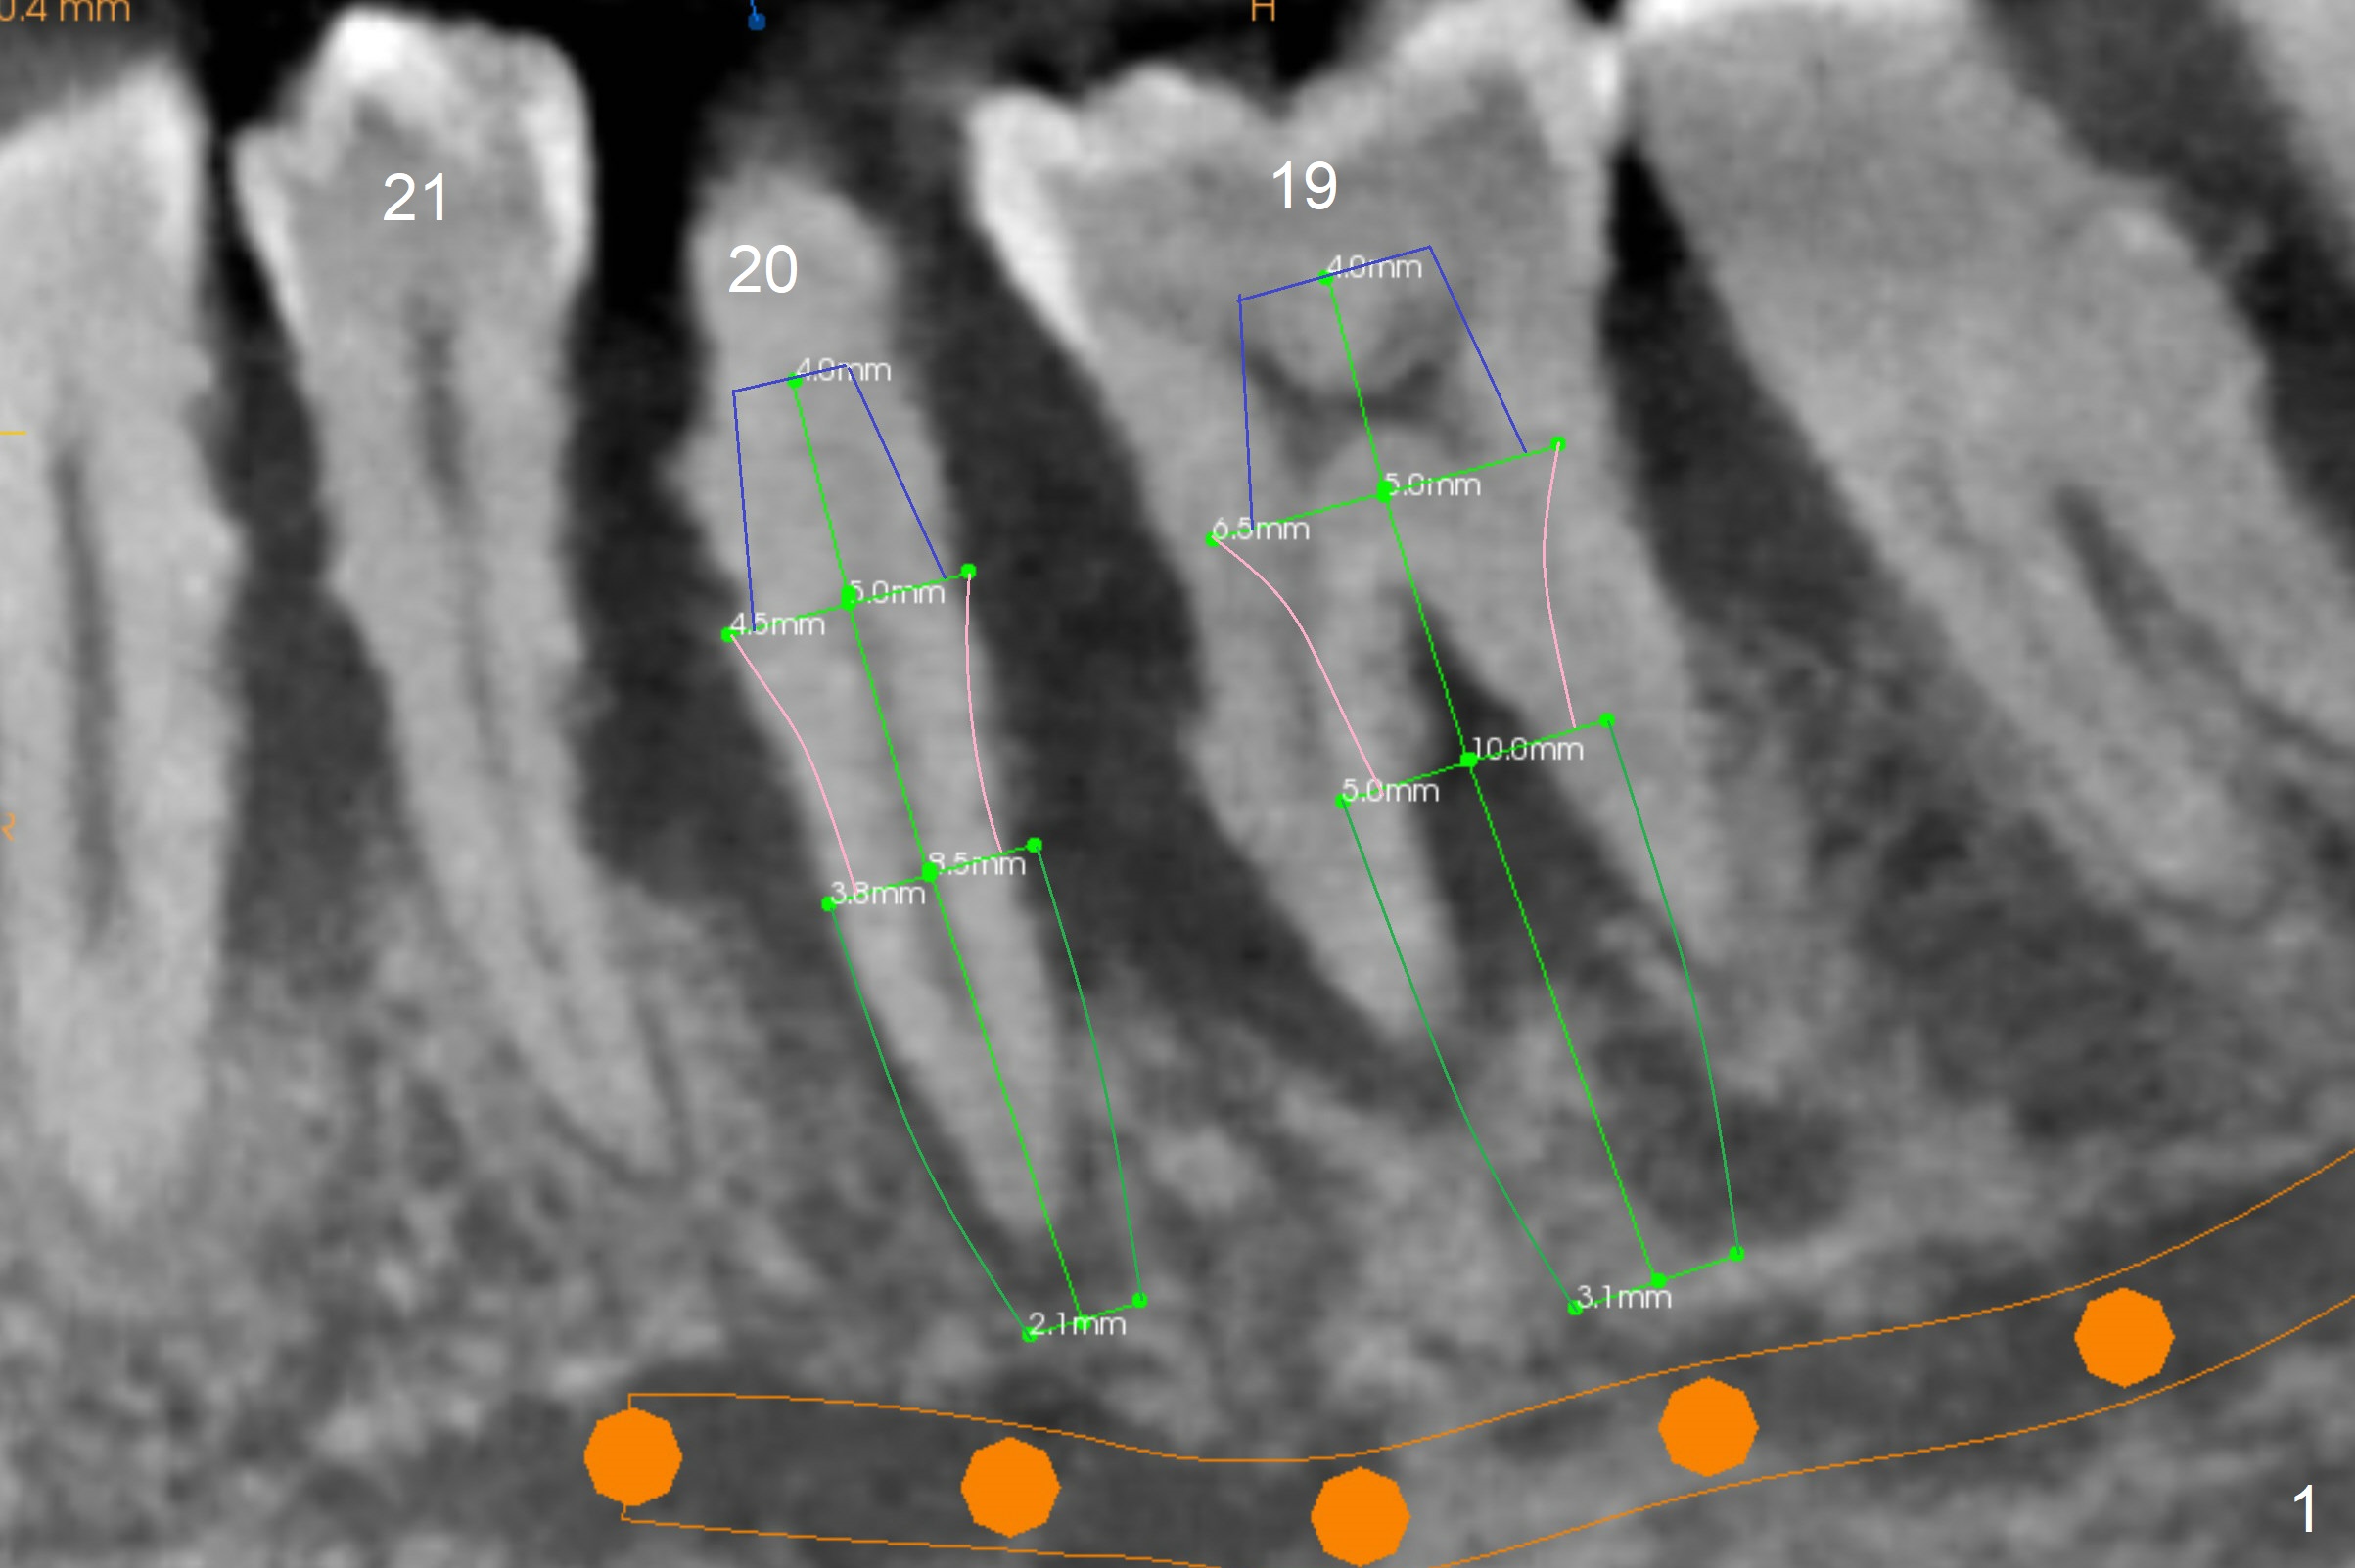

A 36-year-old man develops periodontal abscess at #19 and 20 after scaling & root planing. Since the site of #20 is close to the Mental Nerve, 3.8 mm tap or dummy implant will be used to form osteotomy instead of drills (Fig.1,3). While an implant will be placed in the middle of the socket #20, an implant will be placed as buccal as possible at #19 (Fig.4). If primary stability at #20 is poor, extract the tooth #21 and place a 3.8x10 mm lingually (Fig.2). PRF membrane will be placed prior to bone graft after implant placement (Fig.3 yellow).